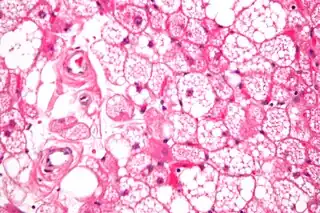

Los tumores se parecen histológicamente a la grasa parda. Se reconocen cuatro tipos histológicos, pero uno es el más frecuente (típico). Se observa un entorno rico en vascularización .

- Tipo lobulillar: grados variables de diferenciación de células uniformes, redondas a ovaladas con células eosinófilicas granulares con bordes prominentes, que se alternan groseramente con adipocitos multivacuolados. Por lo general, hay pequeños núcleos ubicados en el centro sin pleomorfismo. Las células tienen grandes gotas de lípidos citoplasmáticos grandes diseminados por todas partes.[1][2]

Hibernoma (aumento intermedio).